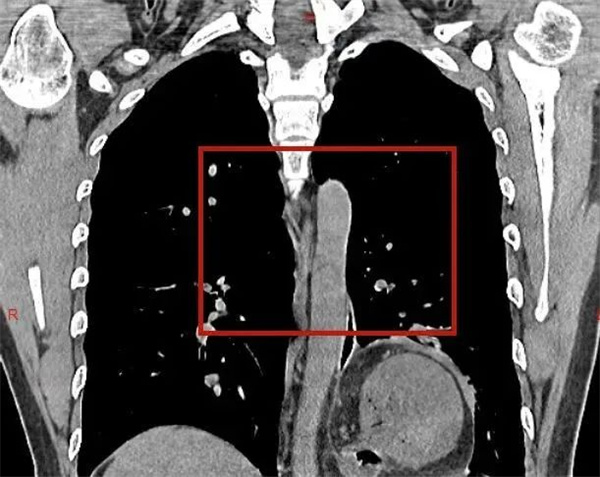

1周前,一位20多岁的年轻小伙来到市人民医院胸心外科肿瘤外科门诊就诊。虽然患者年轻,但是“反酸烧心”不适感已有1年多,经过反复多次的内科治疗,症状时轻时重,均没有得到彻底的缓解。患者打听到市人民医院胸心外科肿瘤外科可以经过手术治疗解除“顽疾”,于是便火急火燎地前来就诊,希望能够解除病痛。经检查明确为“食管裂孔疝”,而且患者疝囊较大,导致胃翻转,出现了难以根治的“反酸烧心”不适。患者入院完善术前准备后,给予“全麻下腔镜下食管裂孔疝修补术+Nissen术”,因为是微创手术,术后患者痛苦小、恢复快,短短几天患者反酸烧心不适已完全消失,感激的对科主任陈瑜说道:困扰他多年的老顽疾,一下子没了,感觉浑身都轻松了,特别感谢胸心外科肿瘤外科团队的精心治疗。

食管裂孔疝、反流性食管炎,一种常见的消化系统疾病;均可引起胃、十二指肠内容物反流入食管引起的食管炎症性病变,导致食管黏膜的损伤,出现反酸烧心、上腹胀痛、胸痛、嗳气等症状,长期会引起贫血;特别是食管裂孔疝,腹腔脏器通过扩大的食管裂孔进入胸腔,压迫肺组织、心脏等重要脏器,产生胸闷气短等严重不适,甚至可能会因为疝内容物的嵌顿,引起消化道穿孔、缺血坏死,出现呕血、黑便、贫血等症状,严重者可危及生命。很多患者朋友出现类似症状后,都选择内科保守治疗,大部分患者通过内科治疗可缓解症状,但也有部分患者内科治疗效果较差,症状持续存在,严重影响生活质量,应明确有无食管裂孔疝;或者需要行食管胃抗反流折叠术,达到更好的治疗效果。目前基本通过微创腔镜完成此类手术,显示更清晰,操作更细致,具有微创、痛苦小、术后恢复好、住院时间短等优点,不但极大的缓解了患者痛苦,同时减轻患者因住院时间长导致的经济负担,被患者普遍接受。